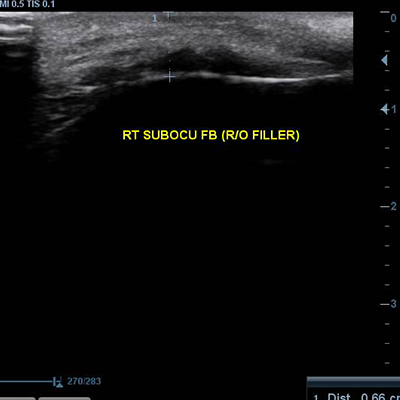

[얼굴이물질제거] 17.02.30 - 이물질제거(윗입술) - 전후사진

17.02.30 - 이물질제거(윗입술) - 전후사진